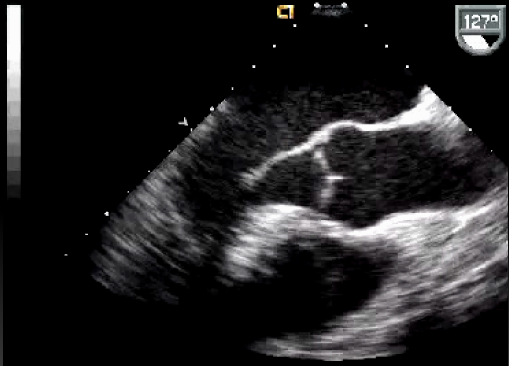

Curso de ecografía crítica en todas sus modalidades (ecocardiografía transtorácica y transesofágica, ecografía pulmonar, vascular, cerebral, FAST) dirigido a: médicos intensivistas, emergenciólogos, anestesiólogos, internistas, médicos de familia, neumólogos, cardiólogos y a todo aquel interesado por utilizar la ecografía como parte del examen físico del paciente crítico.

En nuestro afán por seguir el trabajo empezado hace ya varios años desde Europa (España) por impulsar la ecografía crítica para intensivistas, emergenciólogos, anestesistas, internistas, subespecialistas de obstetricia crítica, neumólogos y todo aquel médico interesado en aprender a utilizar la ecografía como parte de su examen físico, ahora desde Centroamérica (Panamá), hemos escrito el primer libro Latinoamericano-Europeo de ecografía crítica sub-especializado y dedicado exclusivamente al paciente con shock de cualquier etiología (obstructivo, distributivo, cardiogénico, hipovolémico) que involucra todas las modalidades ecográficas: ecocardiografía, ecografía pulmonar, vascular, abdominal, del sistema nervioso central/doppler transcraneal, etc) en el que participan muchos expertos en sus respectivas áreas tanto de Europa como de América y también algunos profesores del EDEC (Diploma Europeo de ecocardiografía / ESCIM- Sociedad Europea de Medicina intensiva).